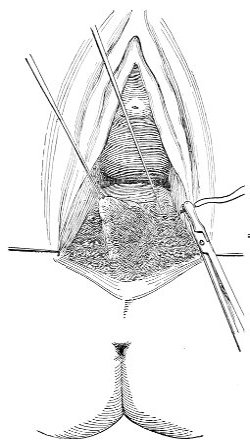

Slight Median laceration of the Perineum.—In this injury the tear takes place through the fourchette. Posteriorly it may extend as far as the sphincter ani muscle. Upward it may extend for an inch up the posterior vaginal wall. The appearance of this tear is shown in Fig. 33. It will be noted that, as this tear takes place in the median line, none of the muscles that support the perineum are involved, nor are the planes of fascia injured. The perineum is slightly split, and the insertions and origins of the muscles and the fascia are slightly separated. The supporting structures of the perineum and the pelvic floor are, however, uninjured.

Fig. 33.—Recent slight median laceration of the perineum: sutures introduced.

If this tear is detected after labor, it should be closed by the immediate operation. A slight tear involving chiefly the cutaneous aspect of the perineum should be closed by three or four sutures introduced from the outside, as in Fig. 33. The needle should be introduced about a quarter of an inch from the edge of the wound. It should not be passed parallel with the plane of the lacerated surface, but should be swept outward and then inward toward the 68 angle at the bottom of the tear (Fig. 34). It may either emerge at the angle and be re-introduced, or it may be passed directly through to the skin-margin on the opposite side of the wound. If the suture is passed in this way, there will be perfect apposition throughout the whole surface of laceration. If the sutures are improperly passed, there may result only apposition of the skin-edges.

Fig. 34.—Diagram representing the correct and the incorrect method of passing the suture for closure of slight perineal laceration.

If the laceration extends up the posterior vaginal wall, two sets of sutures must be introduced—one on the vaginal aspect of the tear, and one on the skin aspect (Fig. 35).